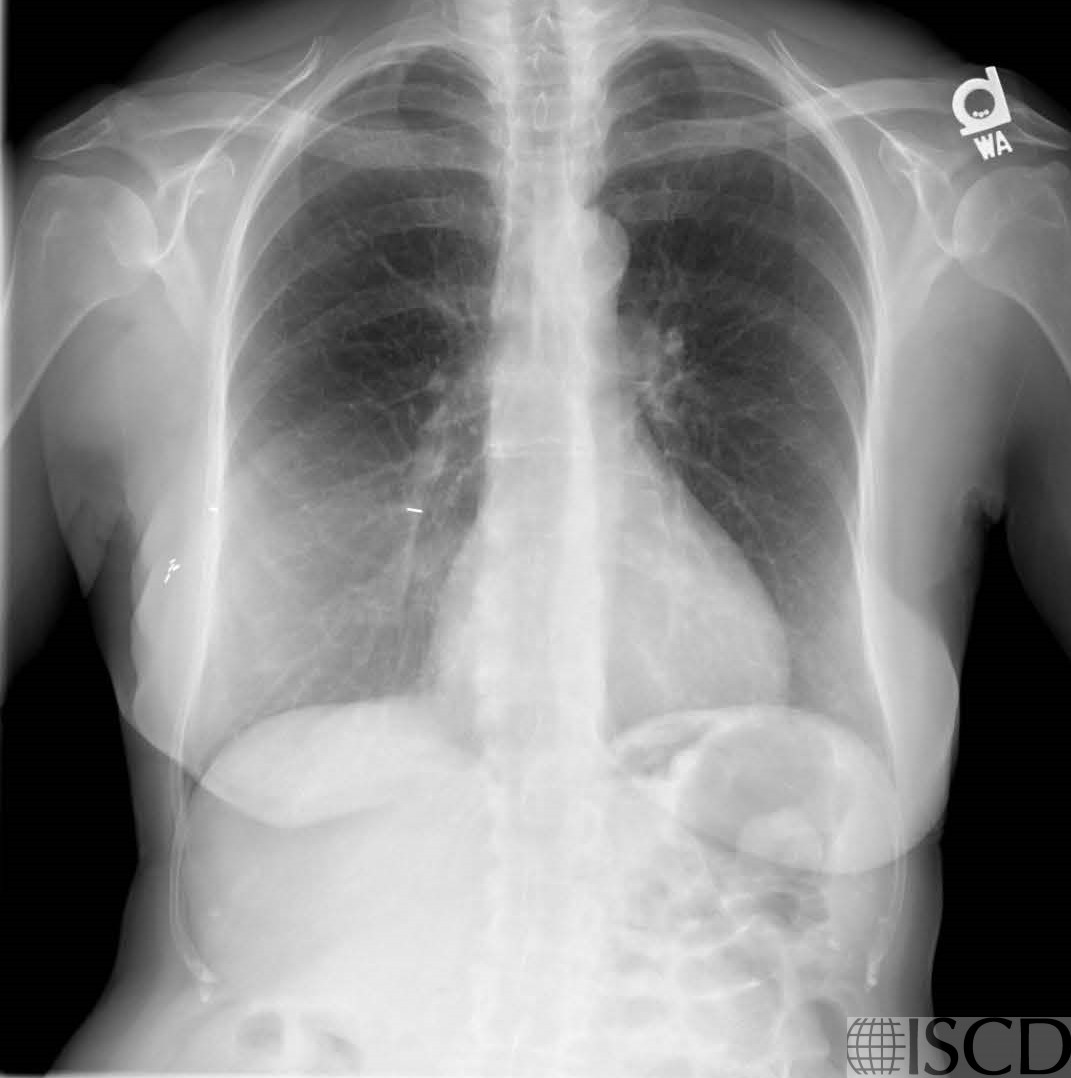

This is the corresponding chest x-ray for the DXA scan showing the breast implants.

This Hologic DXA scan shows a breast implant lateral to L1 on the right. The corresponding undo view shows that the breast implant would be removed from the soft tissue baseline. The correspond chest radiograph shows the implants.